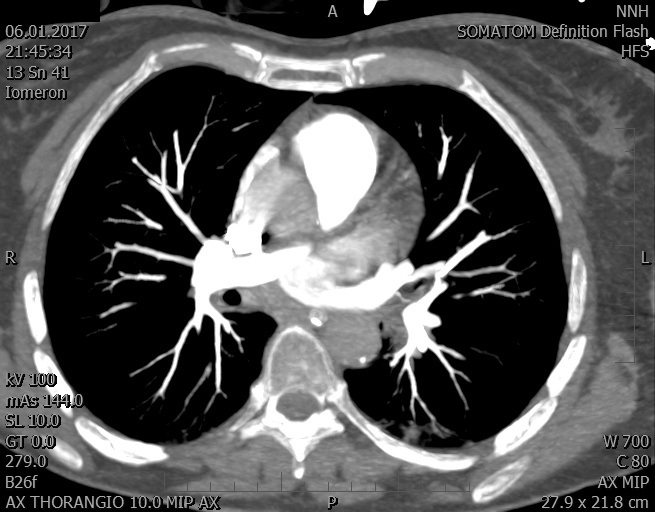

Video 2 - Echokardiograficky byla zjištěna těžká dysfunkce dilatační levé komory s nezvětšenou pravou komorou.Pro nejasnou příčinu zástavy jsme provedli i vyšetření výpočetní tomografií (CT), které vyloučilo plicní embolizaci (série 1 - soubory na konci článku). V den přijetí při přetrvávající oběhové nestabilitě byla nemocná opakovaně defibrilována pro fibrilaci komor se stabilizací rytmu po podání amiodaronu a mesocainu. Dle hemodynamických měření se jednalo o těžký kombinovaný šok. Vstupní laboratorní vyšetření bylo bez větších pozoruhodností. Posléze jsme doplnili anamnézu od příbuzných a zjistili, že pacientka užila do dvou hodin před srdeční zástavou první tabletu amoxicilinu na lehký respirační infekt. Při nevýtěžnosti vstupních vyšetření a nových anamnestických informacích jsme doplnili 14 hodin po kolapsu vyšetření koncentrace tryptázy v séru, která byla extrémně zvýšena (tabulka 2), což nás vedlo k podezření na anafylaxi.